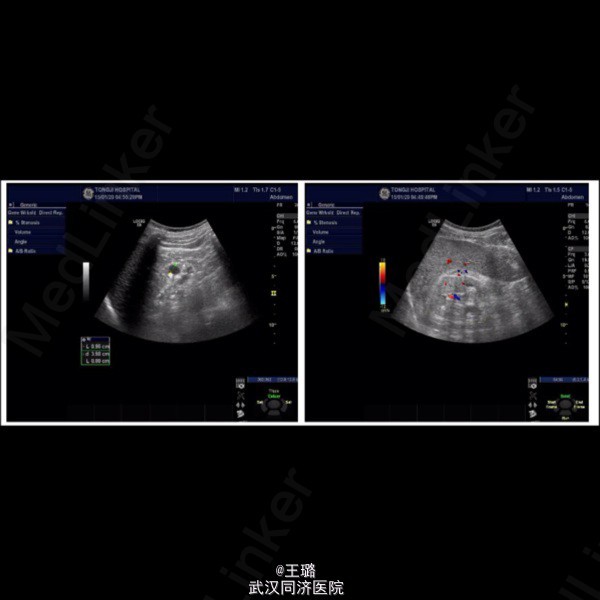

患者,男,62岁,一年前发现尿频、尿急,尿痛,近期出现血尿,遂来我院;B超示双肾结石,左侧多发囊肿,肾萎缩;心脏B超示左心室扩大,主动脉瓣退行性病变。考虑患者自身情况,目前未进行手术治疗。